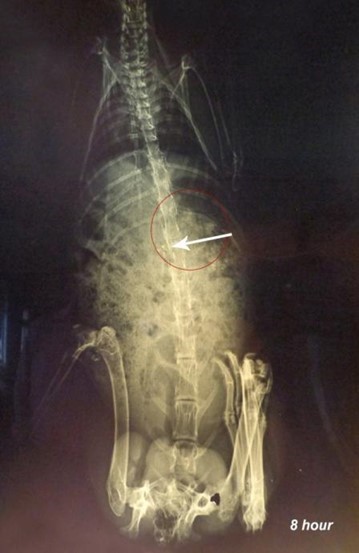

X-ray studies revealed that the microspheres remained in the stomach for the first 2h as shown in fig. (7). Microspheres get released from the capsule shell by dissolving the gelatin shell and distributed in the small intestine as observed in the fig. (8).

Since the particles are small, and the amount of radio-opaque material is also less, the amount of microspheres visible by X-rays is also minimal. Microspheres are visible at 4th h in the small intestine as observed in fig.(8), and some are also seen in the X-ray image taken at the 8th h in the large intestinal region [22]. X-ray image at 10th h indicates the presence of microspheres in the colonic region as seen in fig.(10). The observations were confirmed by a veterinary surgeon. It can be concluded that the formulation is able to target colonic region effectively.

Fig. 8: X-ray image after 4 h